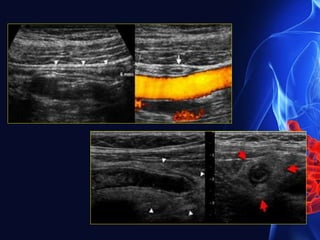

Long Axis Short Axis

TARGET SIGN

USG

Appendicitis

Ultrasound images showing an anechoic blind-ending tubular structure

measuring 10mm in diameter in the right iliac fossa (RIF): this was

found to be non-peristaltic and non- compressible.

An echogenic round body, with posterior acoustic shadowing seen

within the tubular structure, in keeping with an Appendicolith.